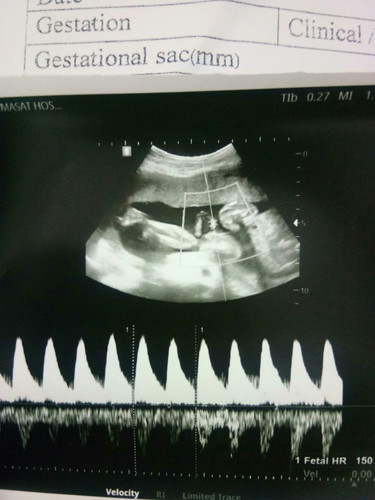

ภาพนี้เปนการฟังเสียงหัวใจน้องค่ะ เหมือนของเราเลย

22w+3 คุณหมอพูดถึงเรื่องร่างกายว่าปกติแค่คุณหมอไม่ได้หันจอมาให้ดู เลยไม่รู้ตรงนี้คือส่วนไหน